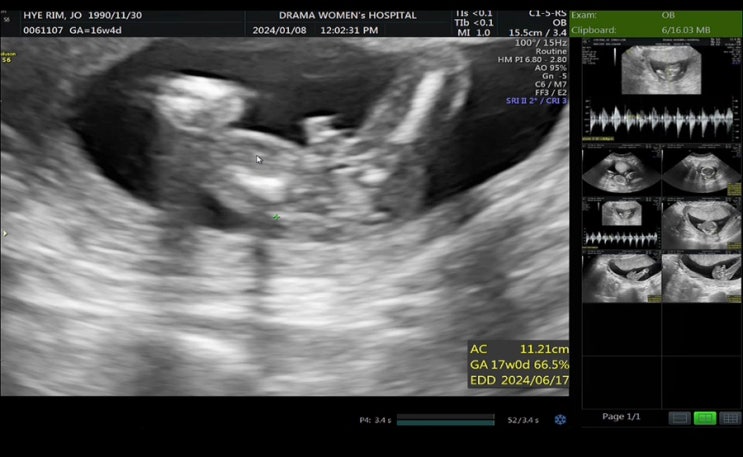

임신 16주차 ~ 18주차 증상 ) 2차기형아검진, 16주차 성별확인, 타병원 전원 결과지 발급받기

16주차 증상 및 검사 16주차 증상 분비물이 좀 더 많아진듯하고 허리가 아프다. 배가 약간 가끔씩 땡긴다. ...